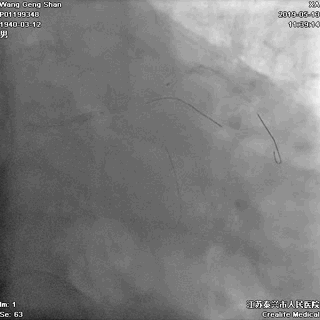

06 LM-LAD支架后扩张

交换回旋支导丝,非顺应性球囊顺序高压扩张